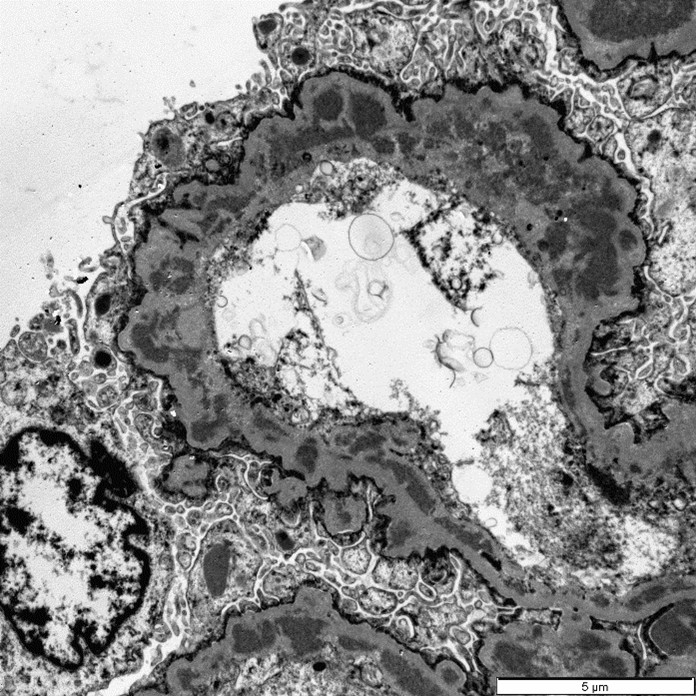

Three glomeruli were available for ultrastructural evaluation by transmission electron microscopy (TEM). One glomerulus had collapsed capillary loops and fibrillary material in Bowman’s space. All glomeruli had numerous large electron dense deposits within the capillary walls in intramembranous, subendothelial, mesangial, and subepithelial locations. Subepithelial deposits were associated with spike-like projections and circulations of glomerular basement membrane material. One glomerulus is segmentally sclerotic with loss of podocytes and denuded capillary walls. The afferent/ efferent arterioles have severely hypertrophied endothelial cells with markedly narrow lumens. In one of the arterioles the circulating erythrocytes are distorted.

Closing out our fourth conference, this case graced participants with an opportunity to see a lovely correlation between light microscopy and electron microscopy (EM) findings. It’s not often that EM images are sent in as part of Wednesday Slide Conference submissions, but it’s always a treat when they are! Many thanks to the contributor for providing both a wonderful slide and beautiful EM images. Together, they truly did paint the whole picture for this EM-worthy condition.Because the EM images were provided, a review of the ultrastructural anatomy of a glomerular capillary profile and its surrounding structures ensued, with focus on the primary and secondary foot processes of the visible podocyte and the different layers of the glomerulus. However, the main show was the electron-dense, granular, irregularly shaped clumps of immune complexes (IC) within subepithelial, intramembranous, and subendothelial spaces of the glomerular tuft. Having IC deposition demonstrably in all three of those locations within the glomerulus assisted with the determination of the “mixed” type of glomerulonephritis in this case. Conference participants favored “membranoproliferative” based on the H&E slide, but acknowledged that this case did not fit 100% into that box upon review of the EM images and accepted the use of the term “mixed” in discussion. Typing of glomerulonephritis is more difficult to do with light microscopy alone due to some histologic similarities between the types, bringing home the point that, for definitive characterization of glomerulonephritis, EM is indispensable.

There was discourse on differentiating membranoproliferative from membranous glomerulonephritis based on histologic features, as some conference participants went one way or the other in their morphologic diagnoses. To summarize, membranoproliferative glomerulonephritis will have an increased number of nuclei within the glomerular tuft, mesangial cell proliferation, and often, the presence of recruited neutrophils. Membranous glomerulonephritis typically just has an increased amount (thickening) of basement membranes. One conference participant inquired on the histologic differences between synechiae and crescents in the glomerulus. Synechiae were described as the touching of the visceral layer of Bowman’s capsule to the parietal layer without fibrosis, whereas crescents have a fibrous component and demonstrate full adhesion of the glomerulus to the capsule. Conference participants did not think there was enough histologic evidence of thrombotic microangiopathy include it in the morphologic diagnosis in this particular case.

Complexes are deposited into glomerular capillaries due to the basement membrane's negative charge. The basement membrane will attract positively charged pre-formed complexes, but can also form IC complexes on itself if a positively charged antigen binds to the glomerulus directly and is then tagged by an antibody.5 The ICs trigger an immune response by either calling in inflammatory cells via their sheer presence or by activating resident glomerular cells to release cytokines, vasoactive substances, and prothrombotic compounds. Either way, this ultimately damages the endothelium, epithelium, and mesangium of the affected glomerulus, resulting in glomerulonephritis.5